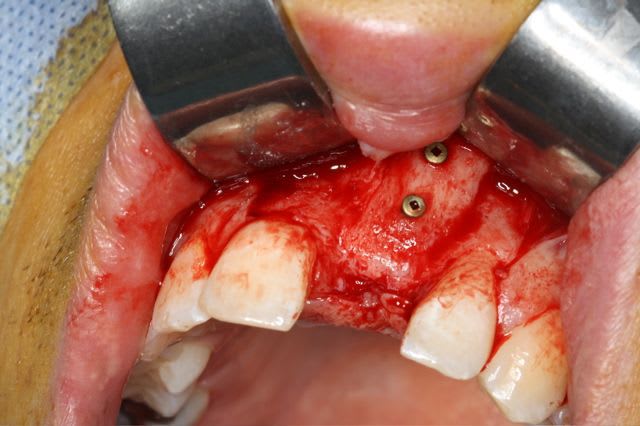

greffe onaly,

dépose des vis et pose de l'implant à 5mois1/2 avec un cj roulé et mise en place de la vis de cica,

pour la greffe: un lit de copeaux généreux et un bloc corticale par dessus et des copeaux pour boucher les espaces. Pas de membrane par dessus, seulement le périoste.